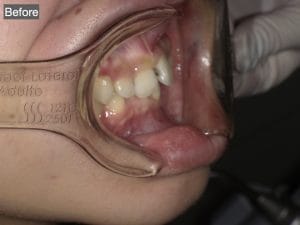

Case032

メジャーリーグでも活躍した元プロ野球選手の山口俊さんのセラミック治療を担当いたしました。

「他院で治療を受けたセラミックが欠けた」というのが主訴でしたが、よく診察するとセラミック欠けただけではなく、被せ物がしっかりと合っていないことが原因で歯茎の腫れがあり、歯石や汚れもつきやすい状態でした。また、歯列も若干歪んでいたので、この機会に全て治療いたしました。

治療後は透明感のある白さで、綺麗な歯並びになりました。また、セラミックをきちんと綺麗に削って適合よくセットしたことにより、歯茎の腫れも改善しました。

セラミックを入れた所の歯茎が腫れていて悩まれてる方はぜひご相談ください。

綺麗に削って適合よくセラミックをしてあげれば必ず改善します。